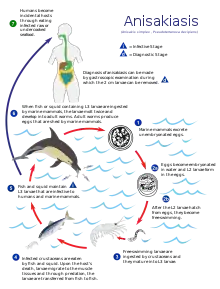

Life cycle

Anisakis species have complex life cycles which pass through a number of hosts through the course of their lives. Eggs hatch in seawater, and larvae are eaten by crustaceans, usually euphausids. The infected crustaceans are subsequently eaten by fish or squid, and the nematodes burrow into the wall of the gut and encyst in a protective coat, usually on the outside of the visceral organs, but occasionally in the muscle or beneath the skin. The life cycle is completed when an infected fish is eaten by a marine mammal, such as a whale, seal, sea lion, dolphin or another animal like a seabird or shark. The nematode excysts in the intestine, feeds, grows, mates, and releases eggs into the seawater in the host's feces. As the gut of a marine mammal is functionally very similar to that of a human, Anisakis species are able to infect humans who eat raw or undercooked fish.

Sexual reproduction occurs once the larvae have reached a definitive host and completed their final molt, at which point sexual organs are developed.[3] Females are capable of producing 2.6 million eggs, depending on species and size at sexual maturity.[4]